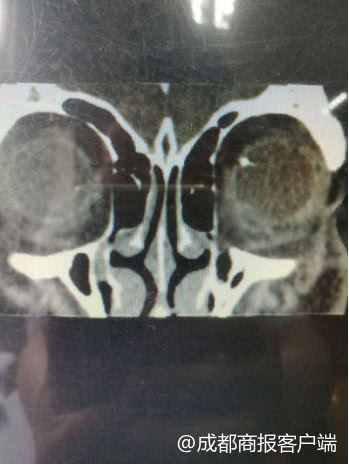

看到章喜安的OTC扫描结果,眼球正后方的黄斑位置正常,但是从眼底照相结果上,王冬梅发现,左眼和右眼对比,看上去有点异样,左眼的左上方稍偏的有一处轻微的水肿。“眼科医生最关心的就是黄斑位置,水肿的位置比较特殊,比较偏,很少会去特别注意到。”王冬梅说。

因为第一次做眼底照相时,没有散瞳,只能看到一部分区域。王冬梅谨慎地建议章喜安入院再做一次散瞳后的检查,章喜安有点犹豫,自己只是眼睛干涩不舒服,应该不会有太严重的问题,怎么需要做那么多检查?“(他)还是在门诊上犹豫了多久,又问他的家属。”王冬梅说,后来,章喜安还是接受了医生建议,入院做了检查。散瞳后检查,医生果然在他的左眼后方发现了一个异物。